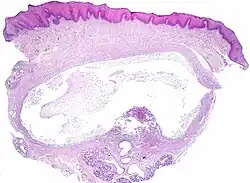

Ranula, micrograph. H&E stain.

The histologic appearance is similar to mucoceles from other locations. The spilled mucin causes a granulation tissue to form, which usually contains foamy histiocytes.[1] Ultrasound and magnetic resonance imaging may be useful to image the lesion.[4] A small squamous cell carcinoma obstructing the Wharton duct may require clinical examination to be distinguished from a ranula.[5]